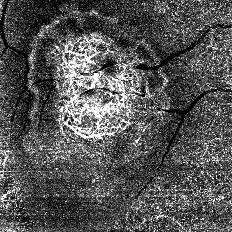

<症例画像>

中心窩下脈絡膜新生血管(CNV:choroidal neovascularization) |

縦分解能3μm※4 の優れた解像度により,網膜血管網を高画質に3D 表示できる。動静脈や毛細血管の走行の上下関係を鮮明に可視化することで,緑内障診断に必要な視神経乳頭内の毛細血管の評価や,加齢黄斑変性で見られる脈絡膜の新生血管の位置を特定するなど,眼底疾病の応用検査として活用されることが期待される。